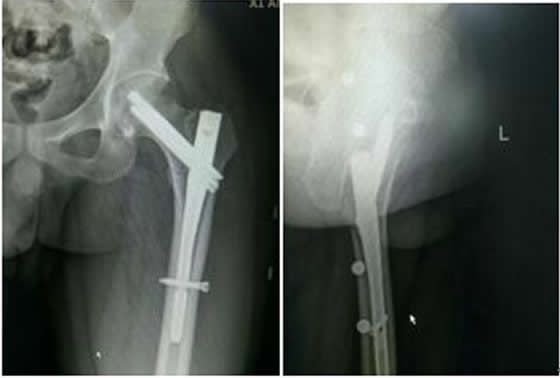

患者稅某某,男,26歲,以“外傷致左髖疼痛、活動受限2小時余”之主訴入院,入院診斷:左股骨近端骨折(A1)。患者于2016.9.19在硬腰聯(lián)合麻醉下行骨折閉合復位InterTan內固定術。手術順利,術后患者恢復良好,現(xiàn)已出院。術后復查拍片如下:

左髖關節(jié)正側位X線片